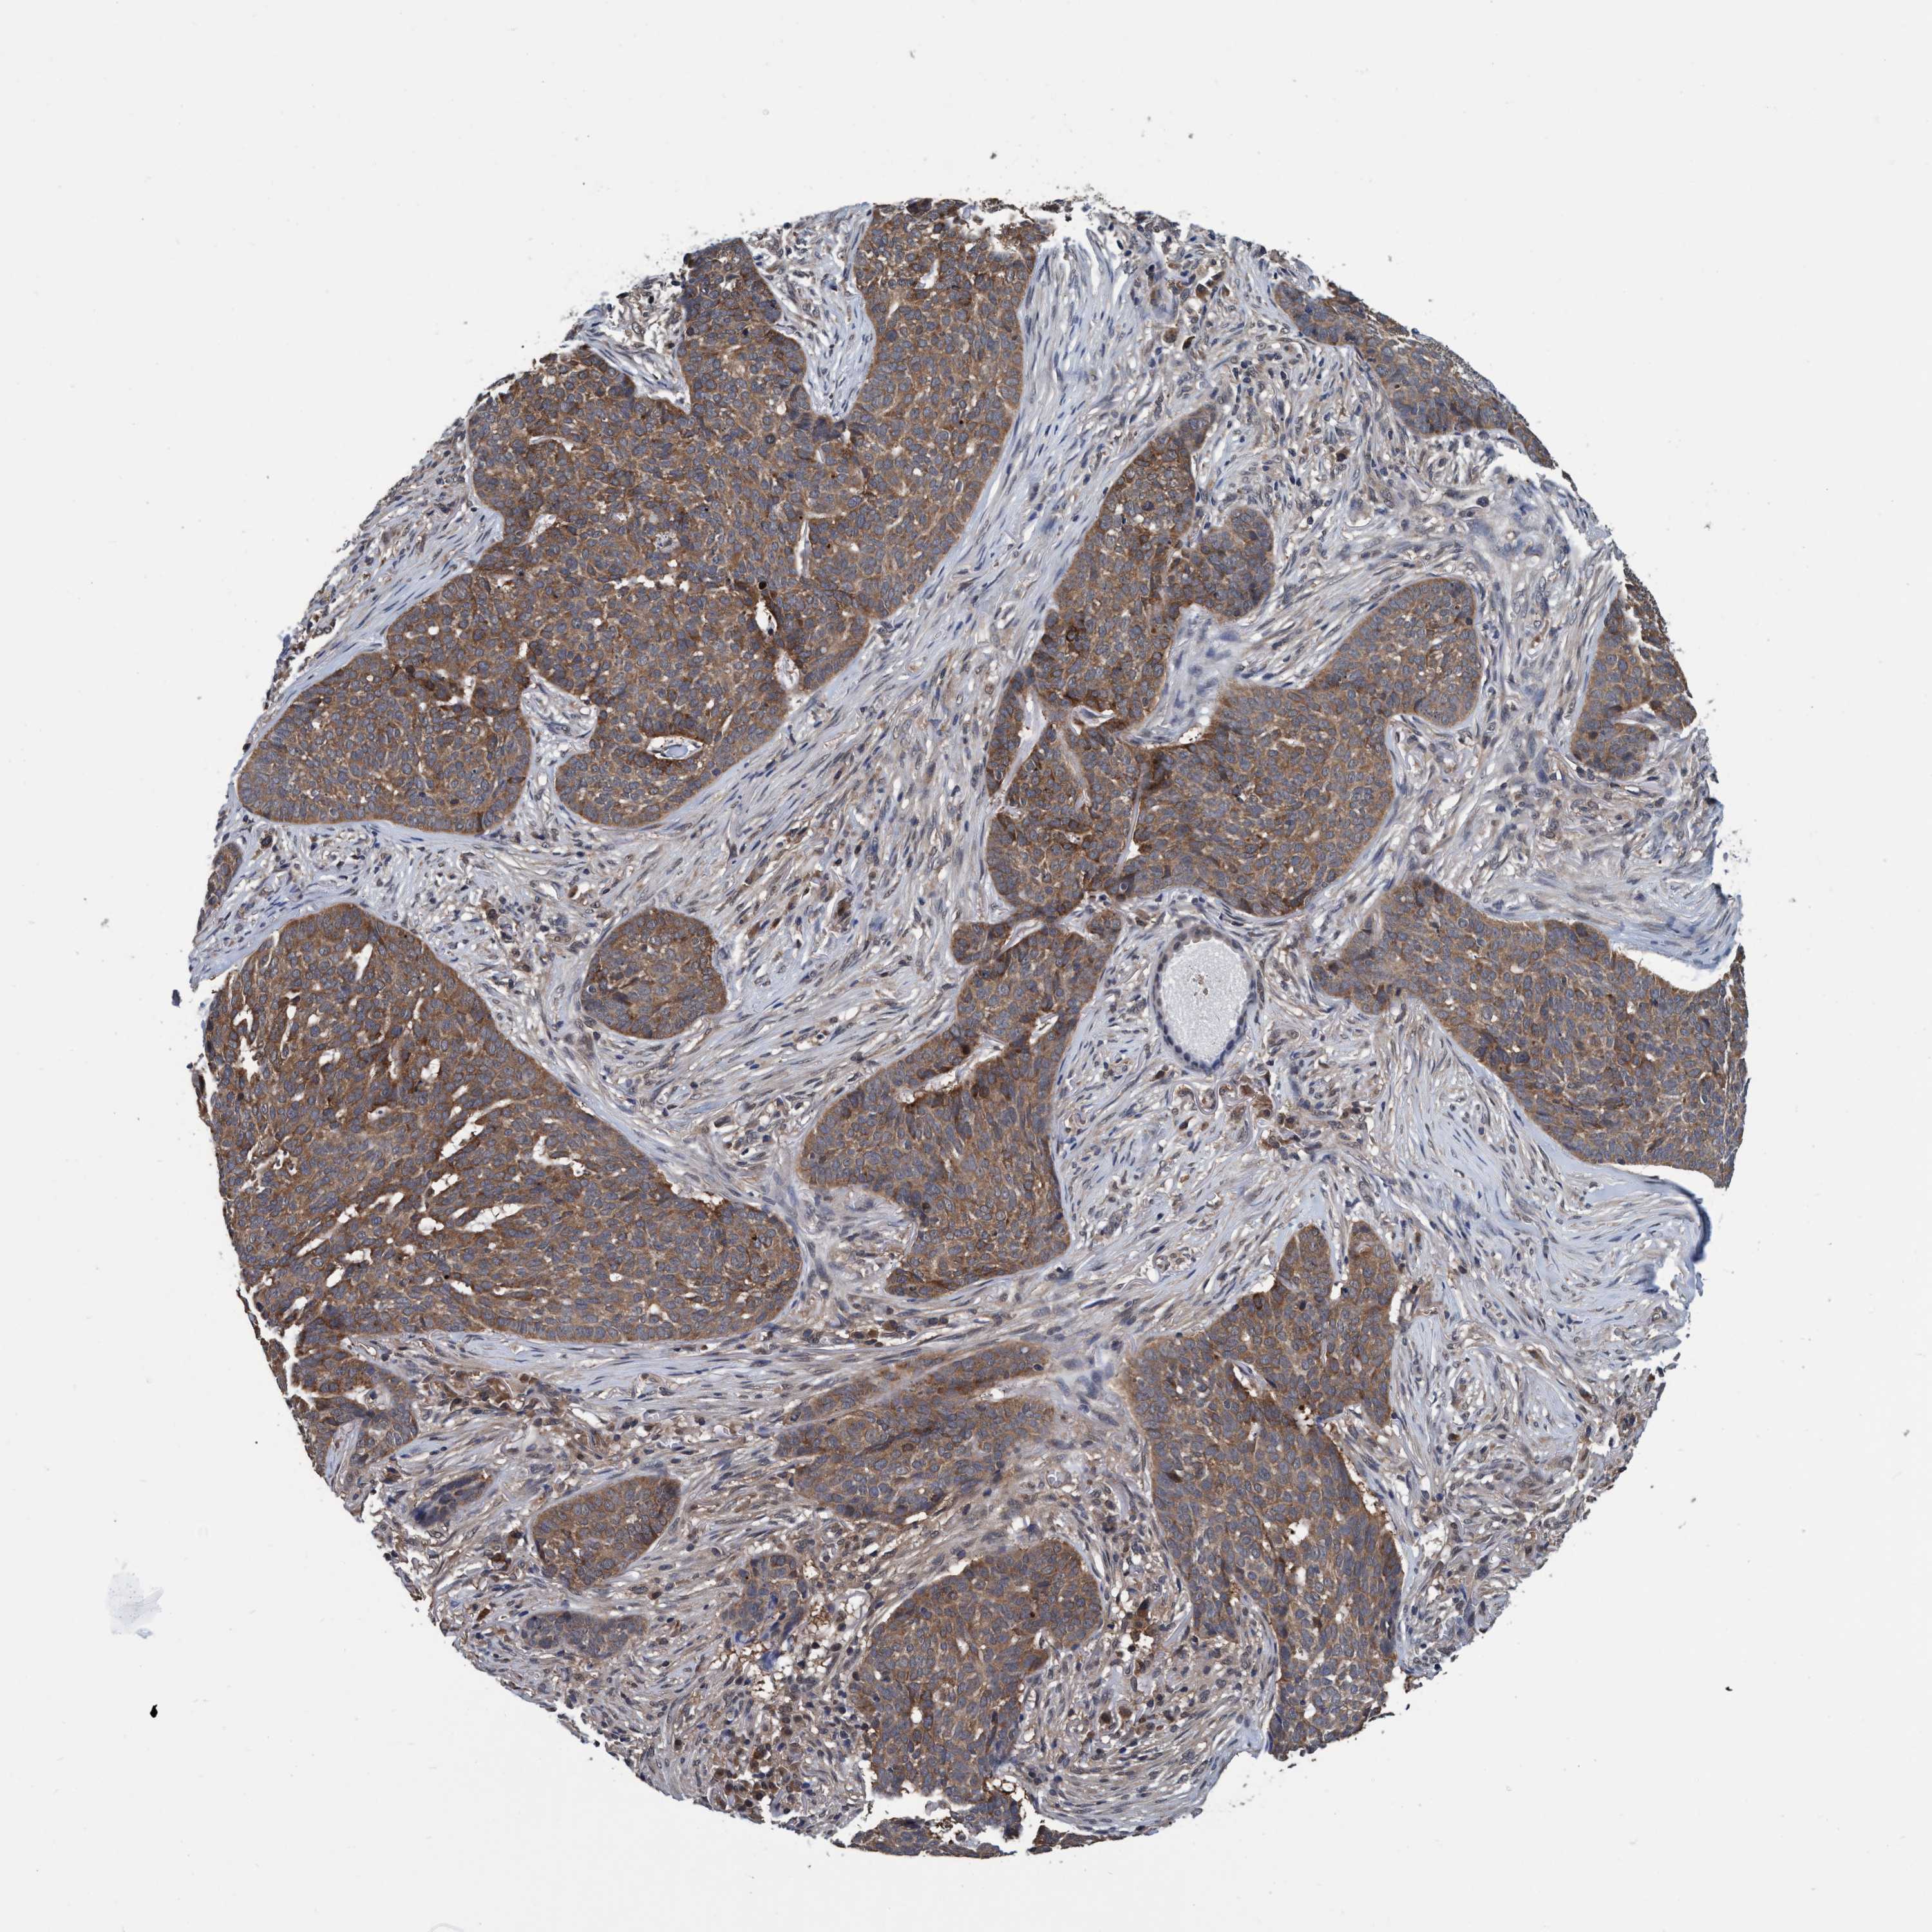

SKIN CANCER - Protein expressioni

A mouse-over function shows sample information and annotation data. Click on an image to view it in a full screen mode. Samples can be filtered based on level of antibody staining by selecting one or several of the following categories: high, medium, low and not detected. The assay and annotation is described here.

Each image is clickable and will lead to virtual microscopy that enables deeper exploration of all samples and also displays staining intensity scores, fraction scores and subcellular localization as well as patient and tissue information for each sample.

Antibody HPA023119

Staining

High

Intensity

Strong

Quantity

>75%

Location

Cytoplasmic/membranous

Squamous cell carcinoma in situ, NOS

Squamous cell carcinoma, NOS

Squamous cell carcinoma, metastatic, NOS

Basal cell carcinoma

Adnexal tumor, benign